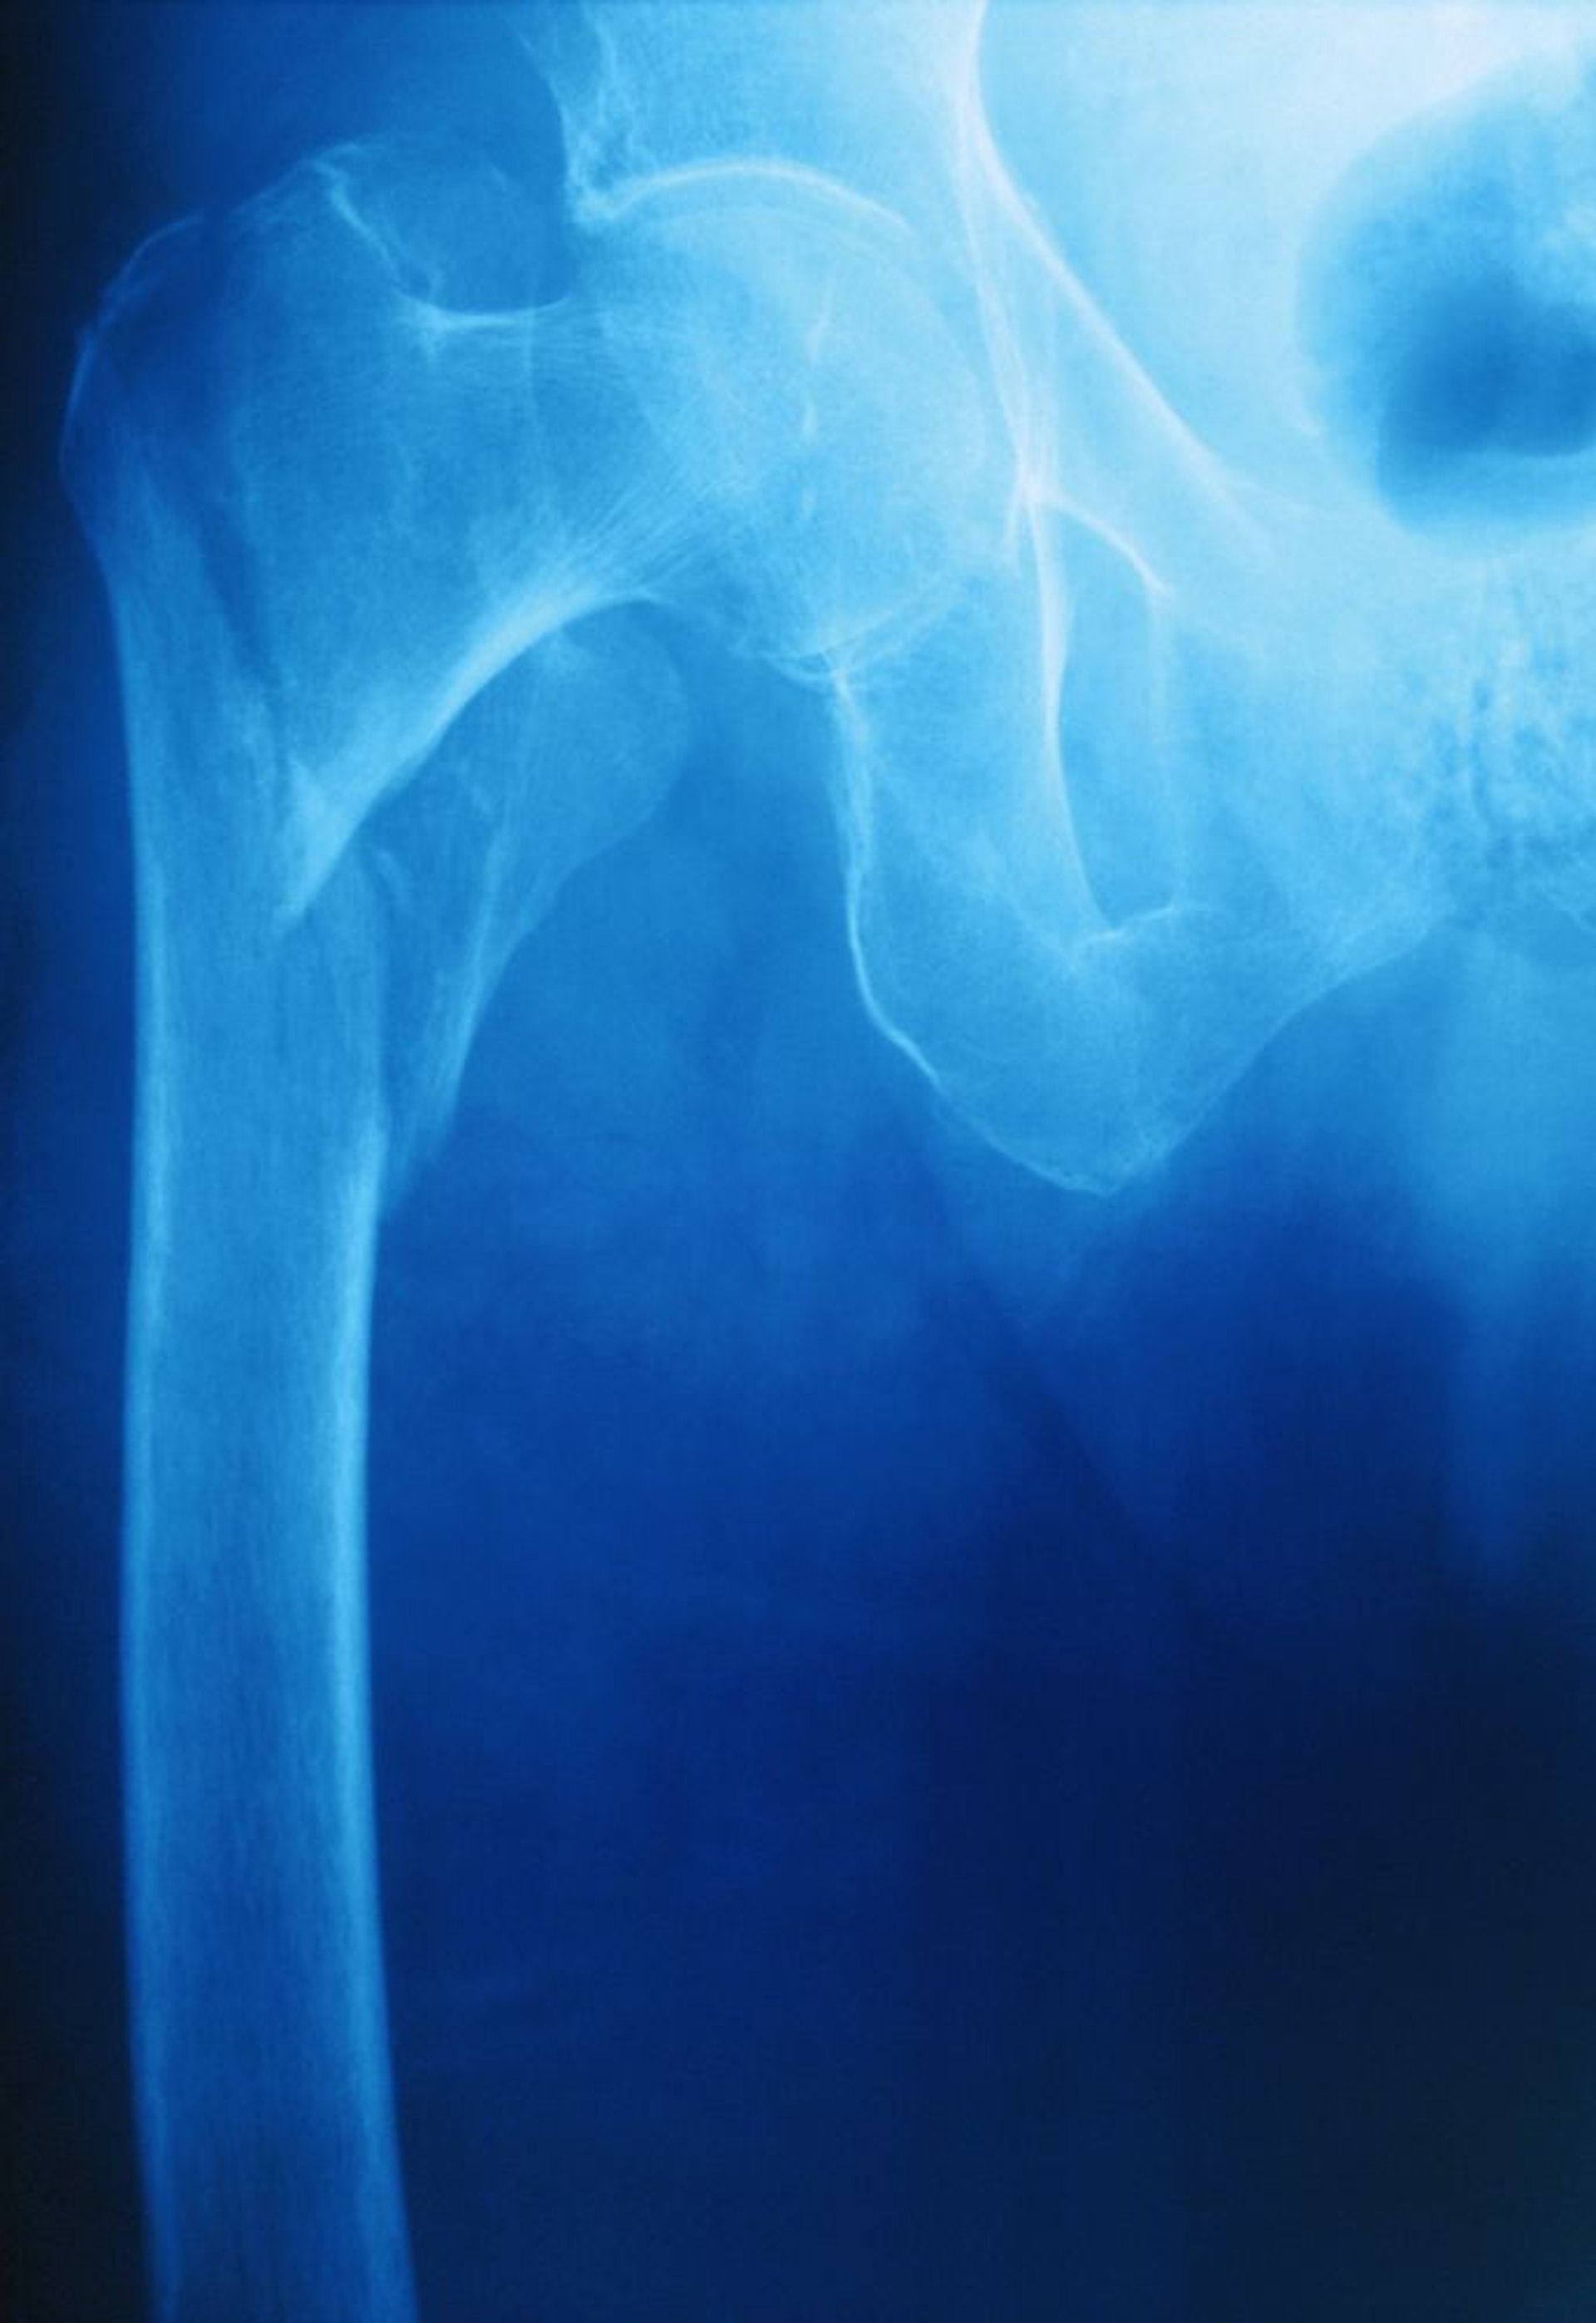

La diagnosi di una sospetta frattura dell'anca inizia con una radiografia del bacino in anteroposteriore e una proiezione laterale diretta. Se viene identificata una frattura, devono essere eseguite le radiografie dell'intero femore. La tenue evidenza di frattura (p. es., come quando le fratture sono minimamente scomposte o ingranate) può includere irregolarità nella densità trabecolare o della corticale ossea del collo femorale. Tuttavia, le radiografie risultano a volte normali, in particolare nei pazienti con fratture sottocapitate o in caso di grave osteoporosi.

Se una frattura non è visibile sulle radiografie ma è sospettata clinicamente, la risonanza magnetica è lo studio di imaging preferito. La risonanza magnetica è più sensibile della TC, la quale può non rilevare fino al 30% delle fratture acute.